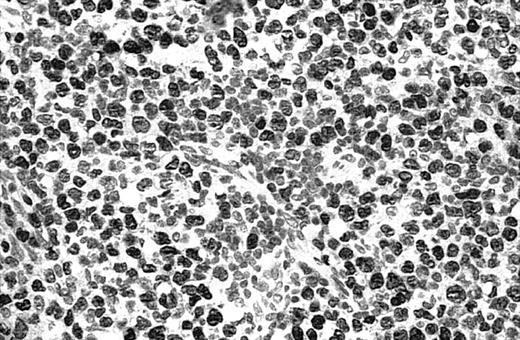

Illustration of IHC staining of JUNB in a C-ALCL patient (case 38).

This photograph (original magnification × 40) showed strong nuclear expression of JUNB by large anaplastic cells with no expression by small reactive lymphocytes.

Of 69 PCLs analyzed by IHC, 44 cases showed nuclear JUNB expression in a proportion of tumor cells (64%) (Table 2). This included 21 (91%) of 23 SS, 6 (75%) of 8 C-ALCL, 5 (50%) of 10 MF, 9 (43%) of 21 PCBCL, 2 (50%) of 4 NK cell lymphoma, and 1 (50%) of 2 systemic FL (Table 2). Seven cases (10%) revealed expression of JUNB by all tumor cells (+++) (overexpression), including 5 C-ALCL (63%) and 2 SS cases (9%) (Table 2; Figures2-3). Epidermal basal and suprabasal keratinocytes also expressed JUNB, which represented a useful internal control to indicate the efficiency of immunohistochemistry (Figure 2). All the positively stained PCBCL cases showed only occasional cells expressing JUNB (+) (Table 2), and in this case it is difficult to conclusively establish whether expression is restricted to tumor cells or activated B cells on morphology.